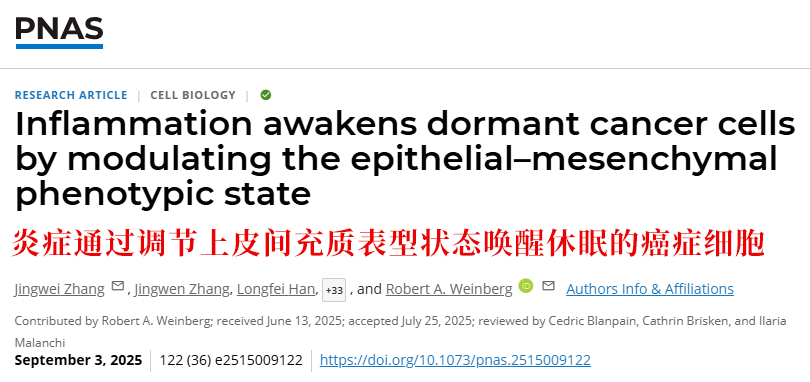

01 PNAS:炎症是唤醒休眠癌细胞的“推手”

2025年9月,中国科学院、麻省理工学院的研究人员在《美国国家科学院院刊》(PNAS)上刊发的一项最xin研究发现:清晰揭示了炎症与癌细胞休眠、苏醒的直接关联。

研究人员利用小鼠进行了实验:首先在实验小鼠身上模拟了乳腺癌发生和向肺部转移的过程,并发现一些癌细胞会进入“休眠状态”——就像进入了深度睡眠一样,这些癌细胞既不分裂增长,也无法形成新的肿瘤病有趣的是,当研究人员在小鼠肺部诱发炎症后,这些原本“睡着”的癌细胞竟被“唤醒”了。

更重要的是,苏醒后的癌细胞自身也发生了明显变化:它们从原本不活跃的状态转变成一种准备行动的状态,重新获得了分裂和形成转移瘤的能力。这一研究直接证实,慢性炎症正是唤醒休眠癌细胞、诱发癌症转移复发的重要诱因。